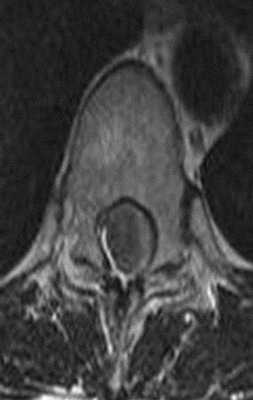

Менингиома на снимке МРТ грудного отдела позвоночника в аксиальной проекции

МРТ грудного отдела позвоночника в аксиальной проекции